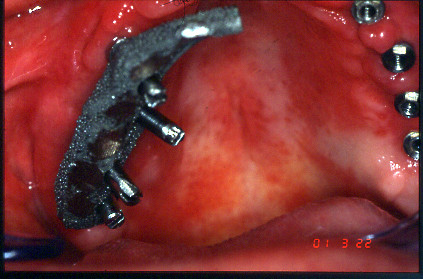

CASO CLÍNICO DE SOBREDENTADURA CON BARRA. MANDÍBULA.

CASO CLÍNICO.SOBREDENTADURA EN MANDÍBULA.

SOBREDENTADURA EN MAXILAR SUPERIOR.